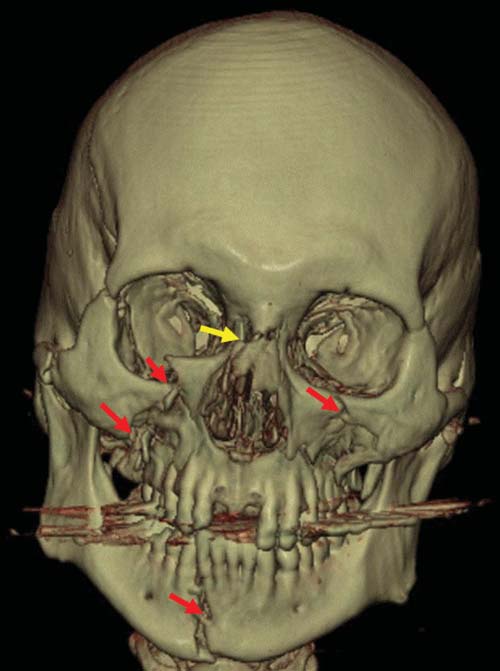

As is well known from clinical medicine, mid-face fractures can also extend over the maxilla and the zygomatic bone (Figure D3.2.8). These fractures arise from a direct impact to the face. Depending on the involved structures, these fractures are classified as Le Fort I-III. This classification can be difficult, especially in cases of vehicle accidents, where, due to the massive damage, multiple fractures are often seen. In such cases, the Le Fort classes overlap (Figure D3.2.9). Mandibular fractures occur due to punches, falls, and vehicle accidents, to name just a few mechanisms. Direct fractures are seen paramedially, whereas indirect fractures are mostly located in the region of the joint and the mandibular body.